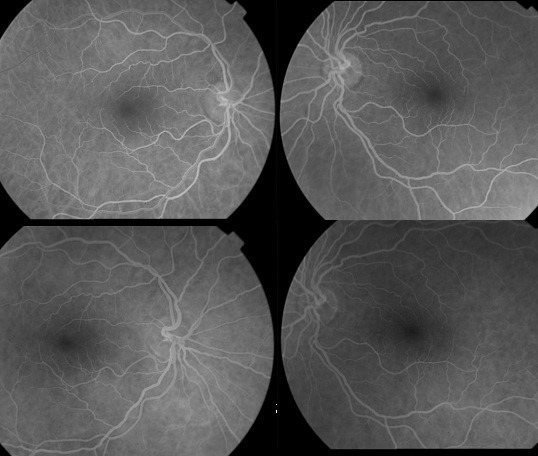

Case description: A 58-year-old woman presented to our clinic with a two-day history of blurred vision in her right eye. She had numerous uveitis attacks previously, and she was on infliximab treatment for ankylosing spondylitis. Her best-corrected visual acuity was counting fingers and 20/25 in the right and left eye, respectively. Optic discs seemed healthy in fundoscopic examination. The right optic nerve showed high signal intensity on magnetic resonance imaging (MRI). Infliximab treatment was discontinued and systemic steroid therapy was started. After the treatment her best-corrected visual acuity improved to 20/20 in her right eye.